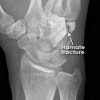

갈고리뼈 골절의 영상 검사

X-ray 검사는 종종 정상으로 판독되기도 하며, 손목굴 영상(carpal tunnel view)에서 보일 수 있습니다.

종종 CT에서 골절이 보입니다.

CT : 갈고리뼈 골절(Hamate fracture)